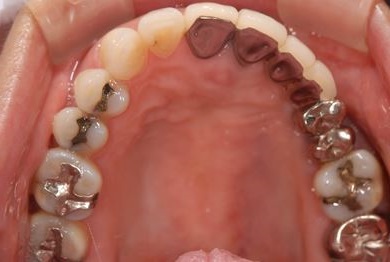

| 性別/年齢 | 女性 / 45歳 | ||||||||||||||||||||||||||||||||

| 治療方針 | 保存不能の歯を抜歯し、インプラント治療にて機能的・審美的回復を行う。 | ||||||||||||||||||||||||||||||||

| 治療内容 | インプラント1本、ハイブリッドセラミッククラウン1本 | ||||||||||||||||||||||||||||||||